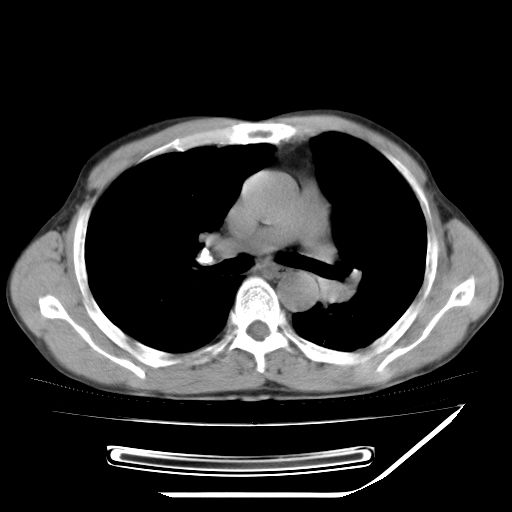

男,59岁,“结核性胸膜炎”30余年,胸部经常疼痛,多次x检查提示“肺部”炎症。腹部疼痛5日,b超提示:“肝内短管结石,余显示不清,建议进一步检查。”

两肺结核并右侧胸腔积液;脾脏、腹腔及腹膜后淋巴结结核[陈旧性];肝内胆管结石

胸部腹部都是结核(双肺。纵隔淋巴结,肝脏,脾脏,肠系膜)